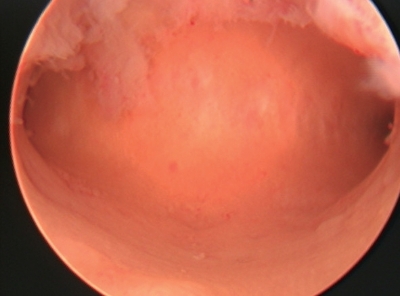

②子宫颈内口:即解剖学内口,呈圆形或椭圆形,内膜比子宫内膜薄,略呈苍白色(图3-3)。